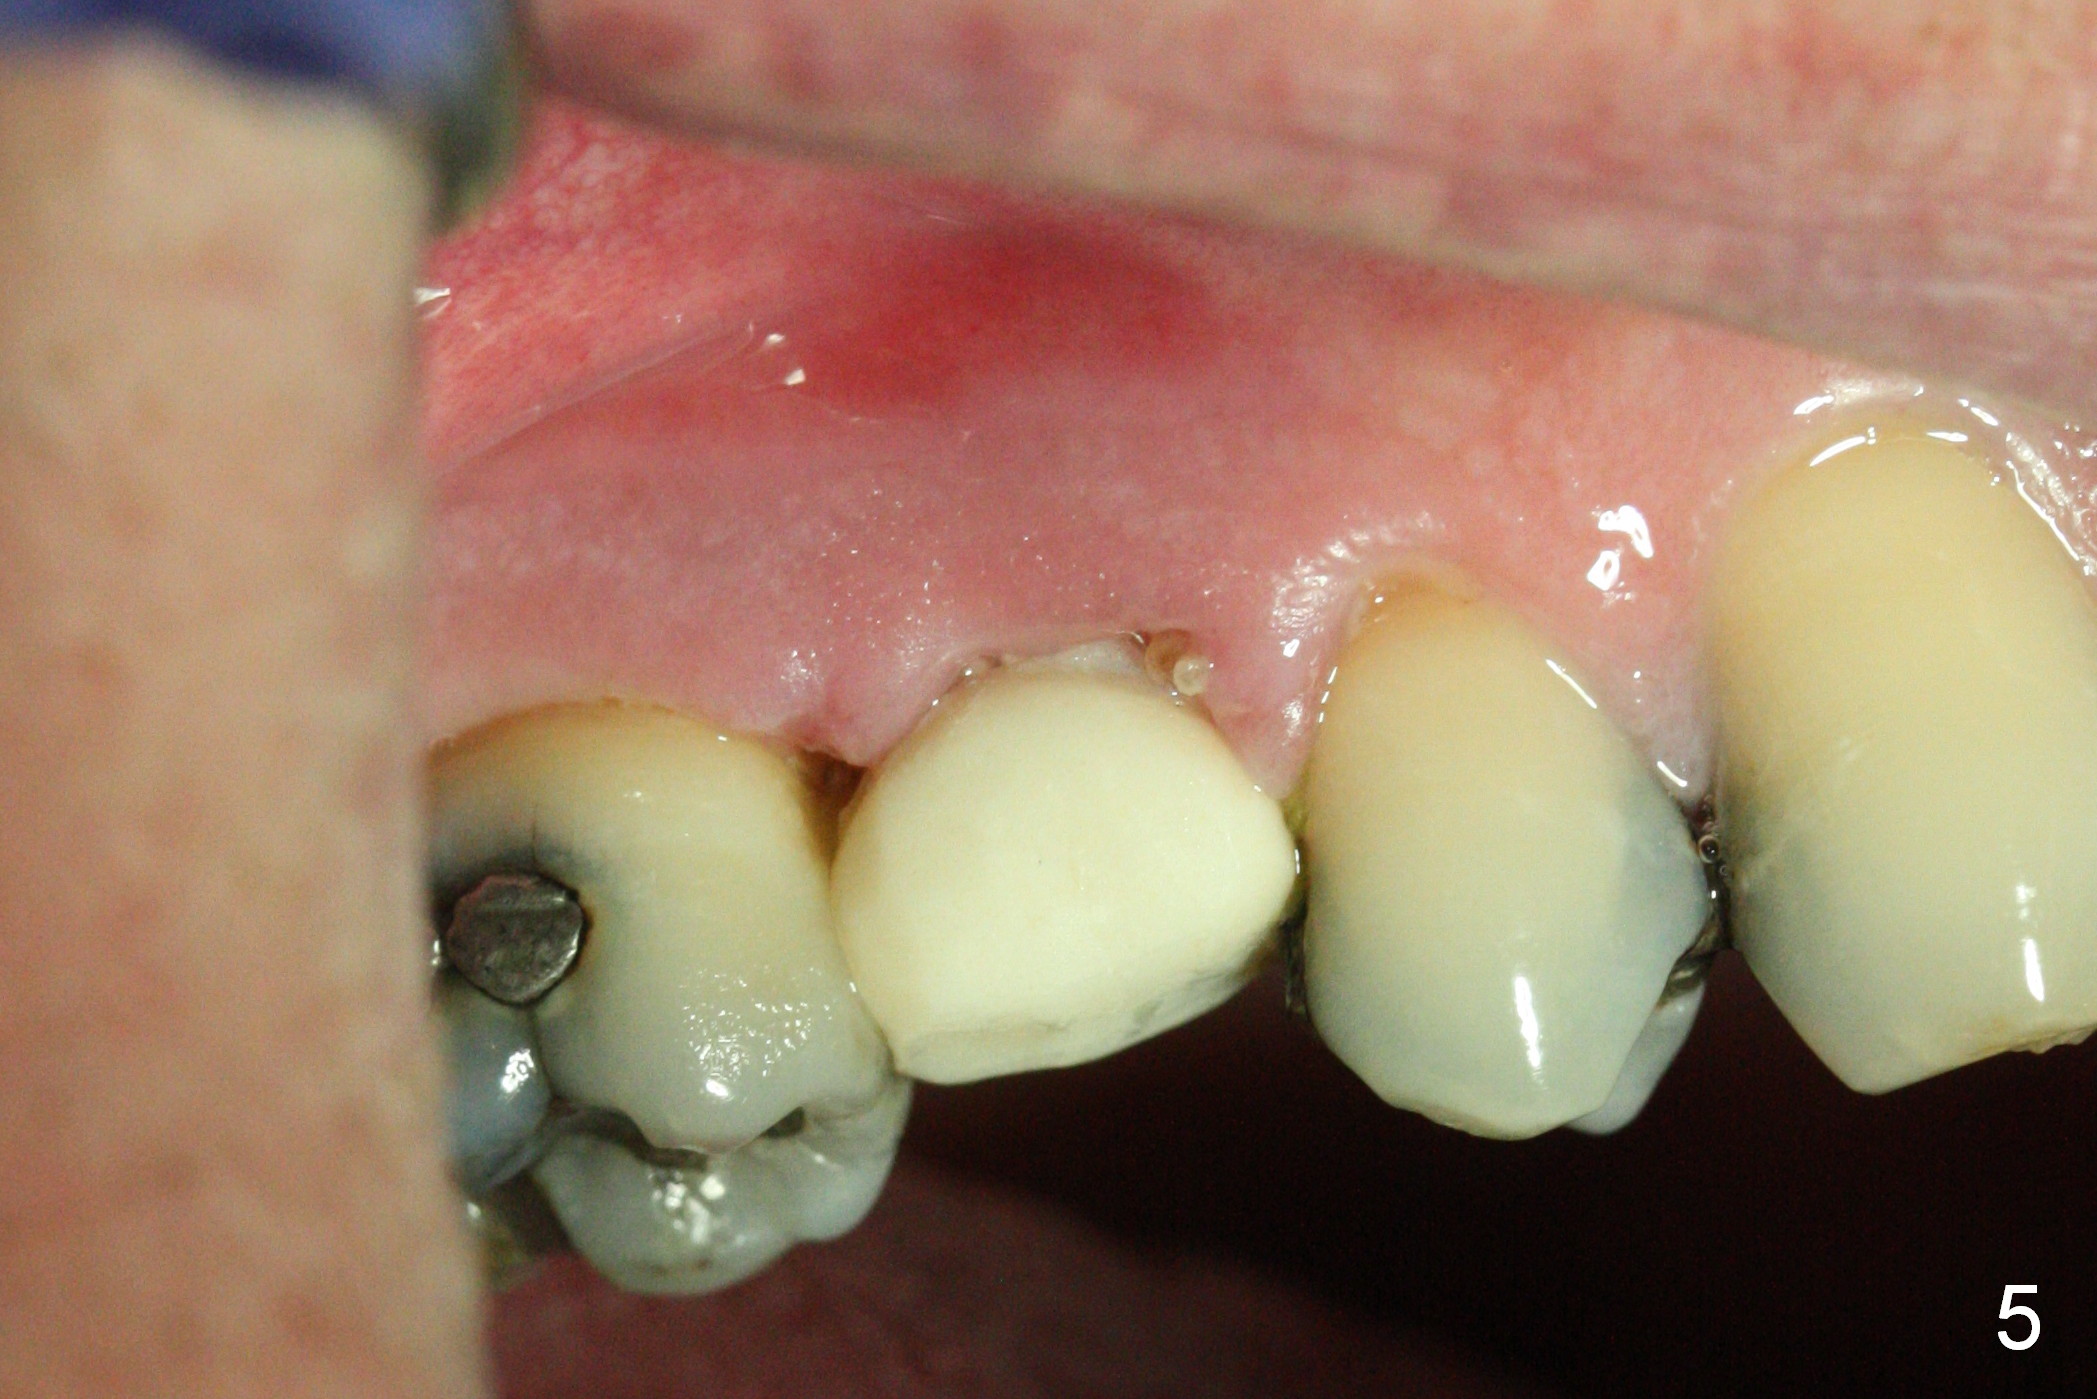

To prevent sinus lift related sinusitis, a shorter implant is going to be placed (Fig.1), approximately 2 mm beyond the apex.  Following extraction, the buccal plate (Fig.3a (coronal section): B) is not only ~ 2 mm shorter than the palatal one (P), but also thinner.  Since the bone density of the palatal plate is higher, without osteotomy an implant is less likely placed in the middle of the socket (S (Fig.1); Fig.3b) than buccal (Fig.3c).  Therefore drills are used to form osteotomy in the apical 1/3 of the palatal slope (Fig.3d (red arrow); SM: sinus membrane).  When 3.3 mm Magic Drill (MD) is in place (Fig.2), the distal surface of the sinus septum is perforated without air leakage.  Demineralized allograft (.0125-.085) is placed for sinus lift (Fig.4 *) prior to placement of 4.5x11 mm implant with ~ 30 Ncm.  The implant is slightly buccal to the ideal position indicated in Fig.3e (curved blue line: sinus lift).  A 4.5x4(2) mm pair abutment is placed for an immediate provisional to hold mineralized allograft in the remaining socket gaps (Fig.4 arrowheads, .5-1.5 mm).  A 9 mm implant may avoid sinus floor perforation on the distal slope of the 2nd premolar.  The osteotomy should have been established initially as mesial as possible.  In fact the patient has nasal hemorrhage while sneezing for the first 2 days postop.  Although he complains of pain buccal to the implant, the gingiva appears to heal 7 days postop (Fig.5).  The distobuccal papilla appears to be displaced somewhat.  Raising mucoperiosteal flap is most likely associated with postop pain and esthetic compromise.  The implant appears to have osteointegrated 5 months postop (Fig.6).  A 4.5 mmx15° 3 mm cuff angled abutment is placed for final restoration.  The distolingual portion of the implant is supported by the regenerated bone 3 years post cementation (Fig.7,8).  There is no bone loss 4 years 2 months post cementation (Fig.9,10).